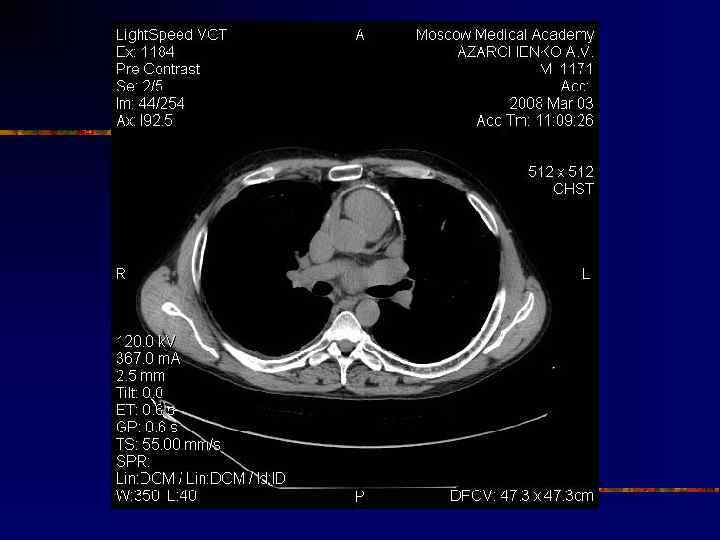

Кальциноз перикарда

Диагноз констриктивного перикардита n n n Кальцификация перикарда Утолщение перикарда n n > 3, 5 мм > 6 мм – высоко специфично n n n Рентгеноскопия (графия) Эхо. КГ КТ МРТ Отсутствуют в 1820% Talreja DR et al. Circulation 2003; 108: 1852 -7